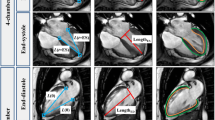

The analysis of the apical and basal tagging images was performed using two different software, Harmonic Phase Flow (HPF) plugin (Computer Vision Center, Barcelona, Spain) [12,13,14] for Osirix Dicom viewer v7.0.2 (Pixmeo, Geneva, Switzerland) and Segment strain tagging module v2.2 R6190 (Medviso AB, Lund, Sweden) [15, 16]. The two software use different technical approaches in analysis of tagging images. Both software required manual epicardial and endocardial segmentation in a single time frame in the plane of analysis.

Segment strain tagging module approaches the tagging pattern analysis in image space, working with non-rigid elastic image registration. The tagging module maps the displacement of single myocardial points between consecutive time frames and presents the displacements of all myocardial points as two-dimensional third-order B-spline tensor products [20]. An inter-frame transformation field is then constructed using a limited memory Broyden-Fletcher-Goldfarb-Shannon optimizer. This transformation field can be used to calculate strains, velocities, and displacements between end-diastole and end-systole of the left ventricle. To solve the displacement or rotation of the left-ventricle wall, cumulating the transformation field through all time frames is required [16]. Torsion in Segment software is defined as the difference between apical and basal rotation, normalized with the distance between the two slices, and the mean radius of the heart wall in these slices. Torsion was calculated in the same way as in HPF for better comparison between the two software.

Results of rotation and torsion data were collected, with respect to time, from end-diastole to end-systole with both software, and exported to MATLAB R2019A (The MathWorks, Inc., Natick, MA, USA) for visualization. Additionally, end-systolic values were collected. HPF reports the relative time as a proportion from 0% (end-diastole) to 100% (end-systole), while Segment uses an absolute time scale. To visually compare rotation curves derived with each software, Segment curves were manually converted in MATLAB to the same 0–100% time scale as in HPF.

The mean analysis time per study was 4 ± 2 min in HPF and 5 ± 2 min in Segment. All cases were applicable for analysis with both software. End-systolic peak apical rotation, peak basal rotation, and peak torsion values were collected (Table 2). HPF showed constantly smaller values than Segment. Looking at the end-systolic rotation and torsion values obtained with different software, similar observations were detected in the study groups. End-systolic apical rotation was smallest in the HCM group (HPF: 1.8° ± 1.8°; Segment: 3.4° ± 4.5°), and end-systolic torsion was largest in the mutation group (HPF: 4.1° ± 1.6°; Segment: 9.5° ± 2.2°). The end-systolic rotation or torsion values were not statistically different between the study groups with either software.

The rotation curves of HCM patients and healthy controls followed similar paths in both apical and basal planes of the left ventricle (Figs. 1 and 2). The largest difference between curves in HPF and Segment was seen in basal rotation in the mutation group (Fig. 2). The other curves agreed well between HPF and Segment. In the apical plane, the end-systolic rotation was higher in mutation carriers than in HCM patients or healthy controls. The rotation curves of mutation carriers were separated from the rotation curves of the other groups in both apical and basal planes. Apical rotation was stronger throughout systole. In Fig. 2, the initial positive basal rotation of mutation carriers was higher than that of healthy controls or HCM patients. Torsion curves of different study groups (Fig. 3) look similar throughout systole.

Absolute rotation and torsion values were significantly different in HPF compared with the respective values in Segment software (p < 0.0001). These values were considerably higher in Segment. Statistically significant correlations were detected in apical rotation, basal rotation, and torsion values between these two software (Fig. 4). The correlation in apical rotation was the strongest (p > 0.9).